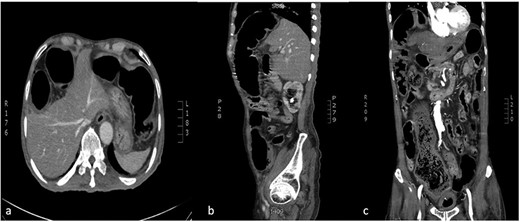

Computed tomography (CT) chest abdomen pelvis with contrast indicated Chilaiditi sign (Fig. 2), large bowel obstruction at the recto-sigmoid junction, colonic diverticulosis, wall thickening at the proximal sigmoid/distal-descending colon and multiple foci of active rectal bleeding.

CT abdomen (a:axial) (b:sagittal) (c:coronal): transposition of a large bowel loop between the right hemidiaphragm and liver denoting Chilaiditi sign.